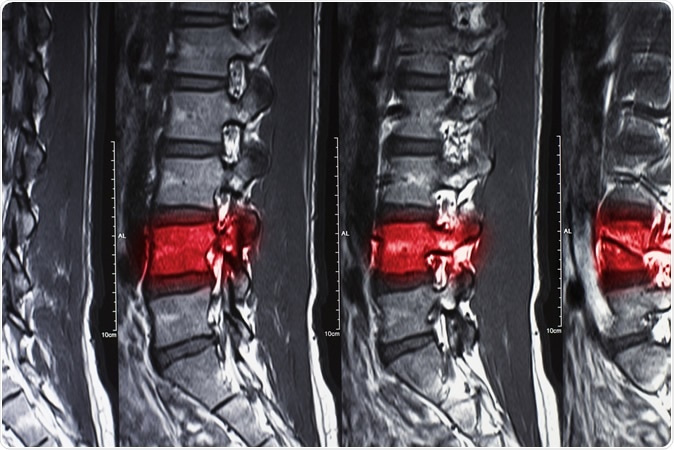

Magnetic resonance imaging of human show fracture and compress spine. Image Credit: SORANAT7 / Shutterstock